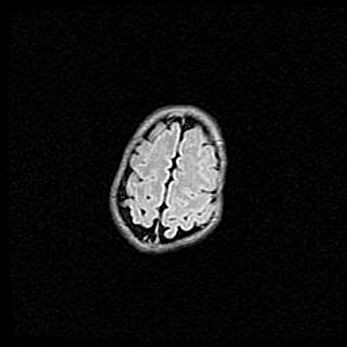

Ниже представлена  галерея МРТ снимков, полученных с применением LMT неонатальных матричных РЧ катушек. Также каждая группа МРТ снимков сопровождается информацией о пациенте (диагноз, возраст, вес, пол, срок гестации) и краткой сопроводительной расшифровкой диагноза.

Неполная лизэнцефалия (пахигирия). Открытая гидроцефалия.

Возраст: 17 дней

Вес: 3110 г

Пол: мужской

Окружность головы: 33,5 см

Срок гестации: 35-36 недель

Лизэнцефалия—недоразвитие корковой пластинки и мозговых извилин в результате нарушения миграции нейронов коры. Поверхность мозговых полушарий гладкая. Микроскопически выявляется отсутствие нормальных слоев коры и скопление групп нейронов в подкорковом белом веществе.

Пахигирия—уменьшение числа вторичных извилин. В пораженном полушарии нервные клетки образуют толстый недифференцированный слой с неправильно расположенными нервными волокнами и группами гетеротопных клеток. Нервные клетки незрелые. Белое вещество истончено. При этом нередко аномально развит корково-спинномозговой путь.